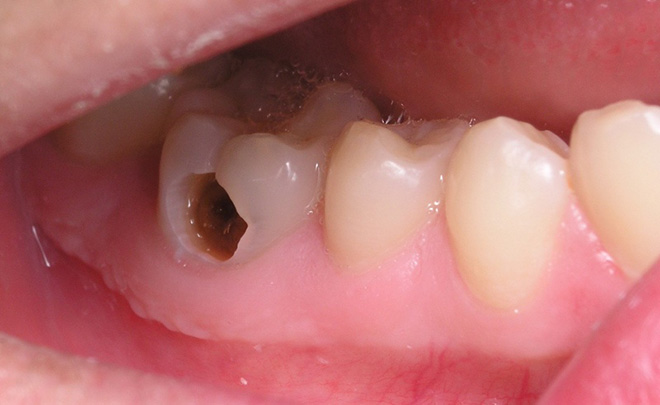

Trám răng sâu giá bao nhiêu là hợp lý?

Câu hỏi: Chào bác sĩ. Răng em bị sâu cũng đã lâu, chỗ răng đau có nhiều vết đen to và lấy tay ấn thì rất đau. Em đã cố…